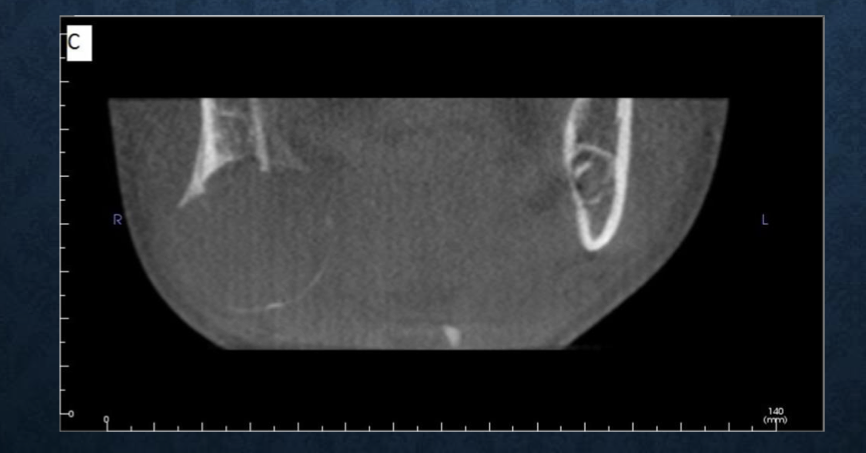

*what is this?

partial volume averaging

a feature of both conventional fan and CBCT imaging

occurs when the selected voxel size of the scan is larger than the size of the object being imaged

aka the borders are so thin that the voxel size gets both soft tissue and bone which it averages together